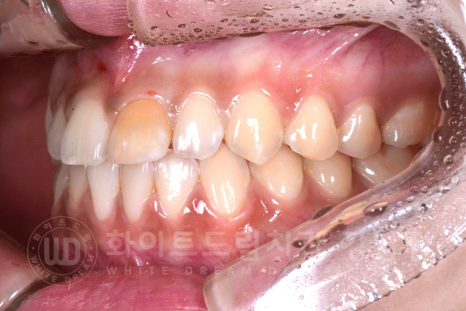

환자분의 구내 사진입니다.

앞니 변색으로 강남역 주변 치과를 찾아주신 환자분의 초기 구내 사진입니다.

환자분의 구외 사진을 보면 대문니 2개가 유난히 큰 토끼 앞니 양상입니다.

21번 치아를 크라운치료하면서, 11번 치아도 라미네이트를 함께 진행하여 심미적인 부분을 개선하기로 했습니다.